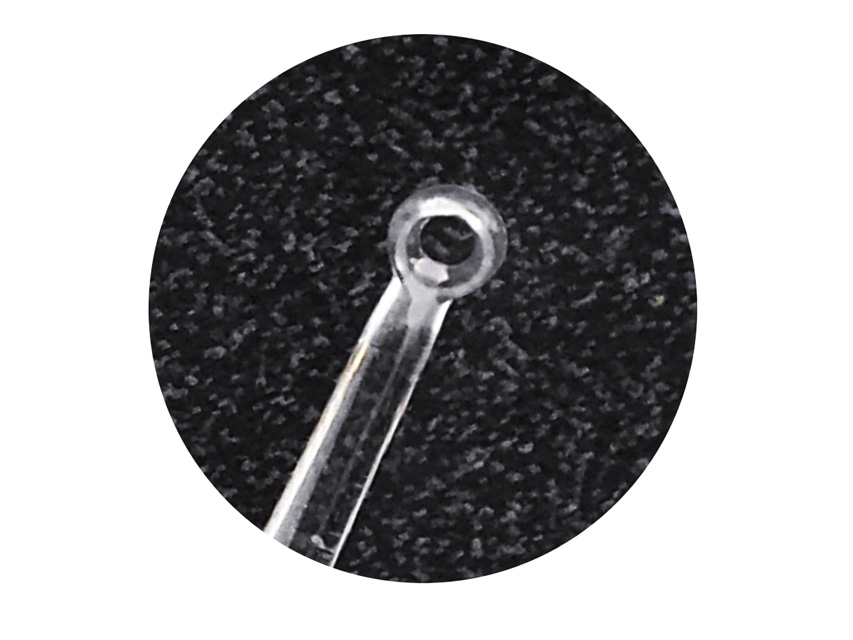

All’interno sono disponibili curettes auricolari, speculum auricolari e speculum nasali, strumenti essenziali utilizzati per l’esame e il trattamento delle vie uditive e nasali in contesti sanitari e professionali.

All’interno sono disponibili curettes auricolari, speculum auricolari e speculum nasali, strumenti essenziali utilizzati per l’esame e il trattamento delle vie uditive e nasali in contesti sanitari e professionali.